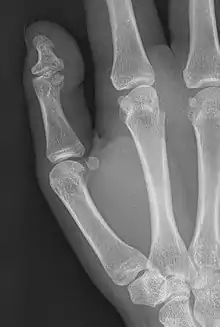

Brachyphalangy of the thumb's distal phalanx, also known as brachydactyly type D, with otherwise normal phalanges of the 2nd-5th digits | |

Brachyphalangy of the distal phalange of the thumb

This condition is caused by either fusion or early closure of the phalange's growth plate. One example is brachydactyly type D, which is caused by an early closure of the thumb's distal phalange, leading to a congenitally short thumb with a similarly short and wide thumb nail.